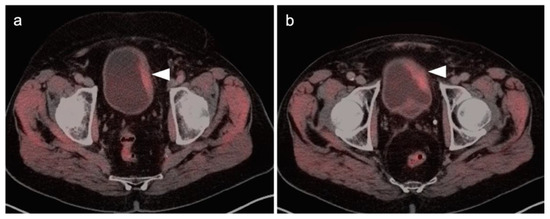

2.5. Vaginal Cancer